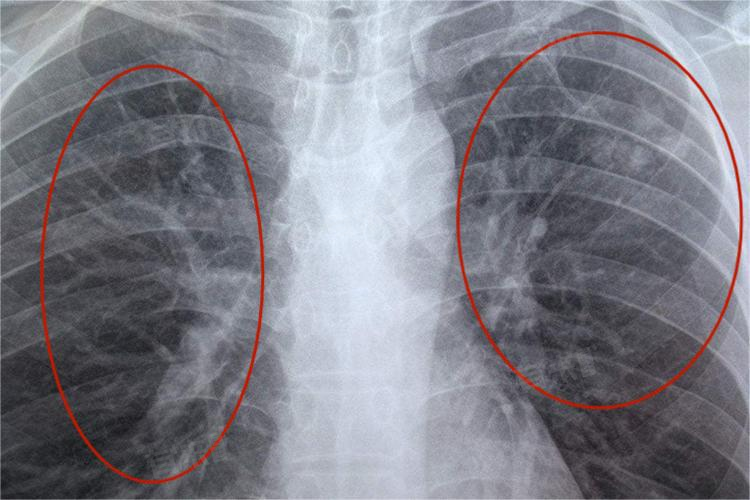

肺部阴影是肺部影像学检查中常见的现象,可能由多种原因引起,包括先天性畸形、陈旧性病变、肺部感染、肺结核、肺栓塞、肺水肿、肺纤维化等。

3、肺部感染:包括由细菌、病毒、真菌等病原体引起的肺炎。这些感染可能导致肺部出现炎症性阴影,通常伴随咳嗽、咳痰、发热等症状。

4、肺结核:由结核分枝杆菌感染引起,多伴随咳嗽、咯血、盗汗及午后低热等症状。结核病灶在影像学上常表现为特定形态的阴影。

9、肺部肿瘤:包括肺癌、肺转移癌等。肺部肿瘤在影像学上常表现为团块状、不规则状阴影,可伴有分叶、毛刺等征象。此外,还有肺炎性假瘤等良性肿瘤也可能引起肺部阴影。

发现肺部阴影后,需要结合患者的症状、体征、病史以及影像学检查结果进行综合评估。必要时可能需要进行进一步的检查,如血常规、血清学检查、支气管镜、肺活检等,以明确阴影的具体原因和性质。